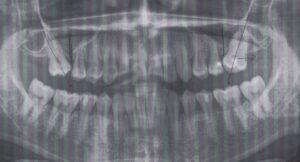

左上第一大臼歯がありません。そのせいか矯正中に第二大臼歯が近心に傾いています。

そのため第二大臼歯近心の下は歯磨きができません。そのため歯が染みています。

矯正中とのことなので第二大臼歯を遠心に移動し、第一大臼歯にインプラントを入れることを勧めました。

矯正中とのことなので第二大臼歯を遠心に移動し、第一大臼歯にインプラントを入れることを勧めました